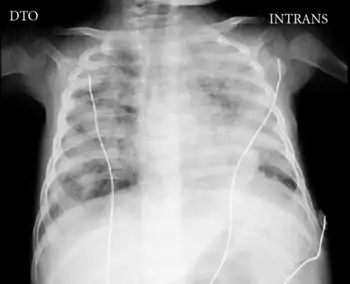

The absence of a thymic shadow on chest X-rays is also indicative of X-SCID.[9] In a normal child, a distinctive sailboat shaped shadow near the heart can be seen.[6] The thymus gland in normal patients will gradually decrease in size because the need for the thymus gland diminishes. The decrease in the size of the thymus gland occurs because the body already has a sufficient number of developed T-cells.[13] However, a patient with X-SCID will be born with an abnormally small thymus gland at birth.[9] This indicates that the function of thymus gland, of forming developed T-cells, has been impaired.